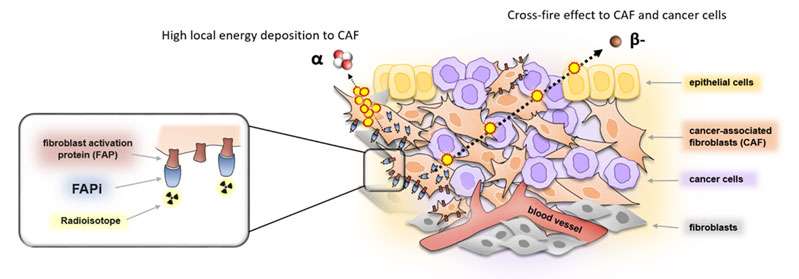

II. Fibroblast activated protein as new target for nuclear theranostics.

Dr Jeremie Calais has designed and initiated at UCLA exploratory clinical studies of FAPI PET targeting the tumor stroma (fibroblast activation protein) in multiple cancers. FAP is a new promising target for nuclear Theranostics.

Figure 4: FAP-target for nuclear Theranostics